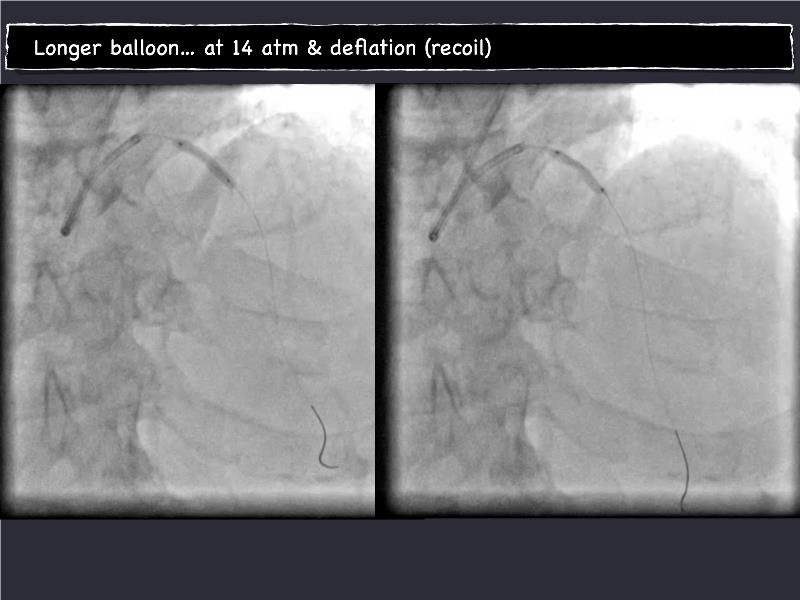

- To understand novel tools and techniques for effective management of bifurcation lesions and long diffused lesions using dedicated stenting solutions